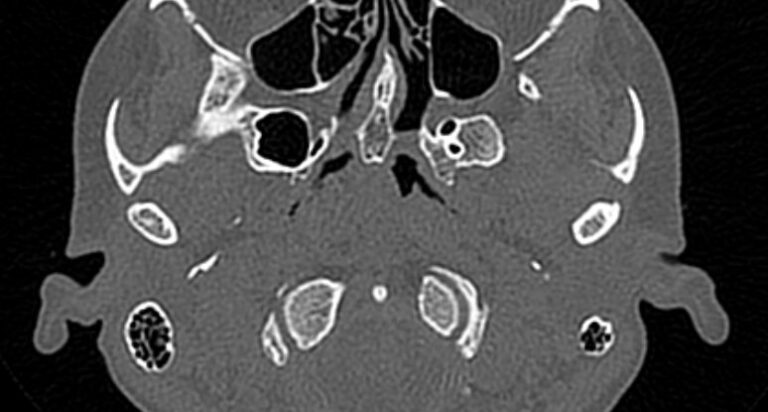

Наиболее точным и информативным методом диагностики костной патологии ВНЧС является мультиспиральная компьютерная томография. КТ относится к лучевым методам исследования, то есть для сканирования применяется рентгеновское излучение. В отличие от обычного рентгена томограф проводит одномоментно множество тончайших срезов исследуемой зоны, которые в дальнейшем проходят цифровую обработку. В результате получаются детальные снимки и трехмерные изображения области височно-нижнечелюстных суставов, которые позволяют проводить точную и достоверную диагностику.

Для оценки функции височно-нижнечелюстных суставов КТ-сканирование проводится в нескольких положениях: с открытым ртом и закрытым ртом. С помощью таких функциональных проб можно оценить положение суставной головки нижней челюсти при движениях нижней челюсти, выявить привычные вывихи и подвывихи суставов.

Компьютерная томография позволяет оценить состояние костных структур височно-нижнечелюстных суставов, так как рентгеновские лучи хорошо задерживаются костной тканью. Для повышения диагностических возможностей компьютерной томографии в ряде случаев дополнительно проводится контрастное усиление путем внутривенного введения йодсодержащего контрастного препарата. Эта методика применяется для улучшения визуализации мягких тканей, которые хуже видны при нативном исследовании.

С помощью КТ можно оценить состояние костной ткани суставных головок нижней челюсти, внутрисуставного мениска, суставной капсулы, связочного аппарата и жевательных мышц.

При проведении мультиспиральной КТ можно выявить следующие патологии височно-нижнечелюстных суставов:

- Травматические повреждения (переломы, вывихи или подвывихи суставов, растяжения связок);